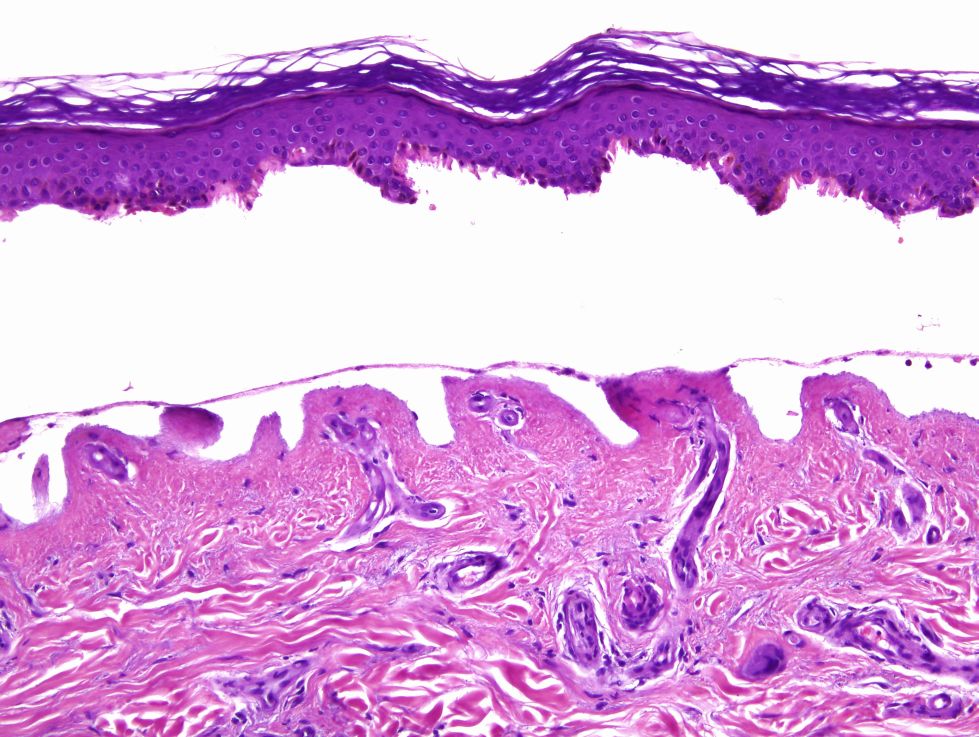

Cas dermatopatologia. Un cas adequat per a aquesta estació de l'any

Gener 2013

Podria suggerir-se el diagnòstic sense conèixer l'historial clínic?